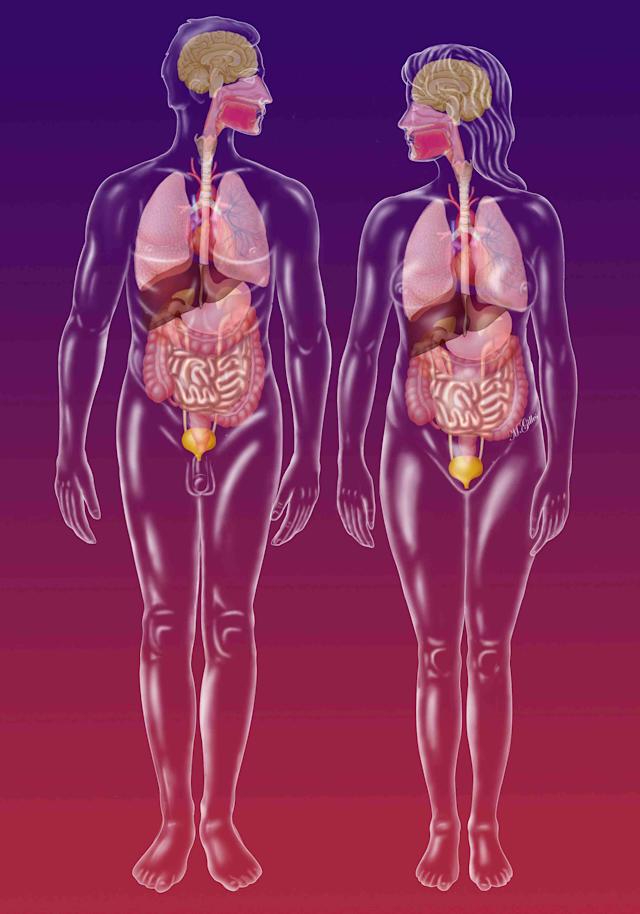

Η Elsevier λέει ότι το τρισδιάστατο γυναικείο μοντέλο της περιλαμβάνει τις ακόλουθες σαφείς διαφορές από τα μοντέλα ανδρικής ανατομίας: Το σκελετικό σύστημα θα προσαρμόσει τις αλλαγές που αντικατοπτρίζουν τις οστικές γωνίες που παρατηρούνται συνήθως στο θηλυκό και θα δείξει διαφορές σε περιοχές που διαφέρουν από τους άνδρες, συμπεριλαμβανομένης της λεκάνης και του κρανίου

Τα αναπαραγωγικά όργανα από τα εσωτερικά και εξωτερικά γεννητικά όργανα έχουν επίσης αναδιαμορφωθεί Συγκριτική λειτουργικότητα. Η έκδοση ανέφερε ότι οι χρήστες μπορούσαν να αλλάξουν μεταξύ ανδρικών και γυναικείων μοντέλων για να επιτρέψουν τις συγκρίσεις στις διάφορες δομές και συστήματα.

Η έκθεση ανέφερε επίσης ότι η τρισδιάστατη γυναικεία ανατομία προσφέρει στους εκπαιδευτικούς μια πιο ολοκληρωμένη προσέγγιση διδασκαλίας και τους δίνει την επιλογή να αλλάξουν εύκολα μεταξύ της διδασκαλίας της γυναικείας και της ανδρικής ανατομίας στο πρόγραμμα σπουδών τους για συγκριτικούς σκοπούς.